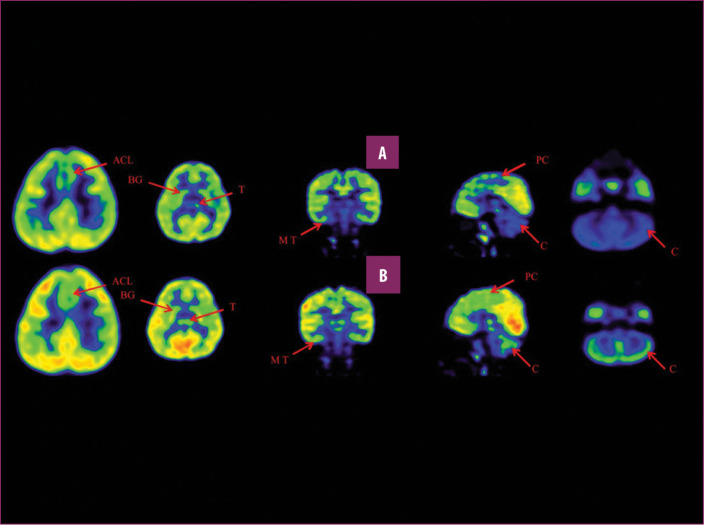

前扣帶回 (ACL)、頂葉皮層 (PC)、內(nèi)側(cè)顳葉皮層 (MT)、基底神經(jīng)節(jié) (BG)、丘腦 (T) 和小腦 (C)。B 行)第一次移植后6個月后PETCT腦部掃描的干預(yù)后圖像顯示標(biāo)記區(qū)域有所改善。藍色代表代謝減退區(qū)域。綠色代表正常的新陳代謝區(qū)域。圖A和B的比較顯示藍色區(qū)域顯著減少,綠色區(qū)域增加,這表明大腦的新陳代謝得到改善。

與之前的情況相比,他在矢狀面和額狀面上的體重變化有所改善;頭部、軀干和骨盆的排列也得到改善,雙側(cè)腿筋和小腿肌肉的緊繃感也有所減輕。患者開始執(zhí)行雙手任務(wù)。在認知方面,由于他定期上學(xué),他的注意力持續(xù)時間和久坐耐力也得到了改善。GMFM評分從60.67提高到67.75;GMFCS等級由Level3提升至Level2;和FIM評分從97分提高到99分。在比較第一次細胞治療之前和之后七個月期間進行的腦部PETCT掃描結(jié)果時,前扣帶葉、頂葉皮層、內(nèi)側(cè)顳葉皮層、丘腦、基底神經(jīng)節(jié)和小腦(表格1)。